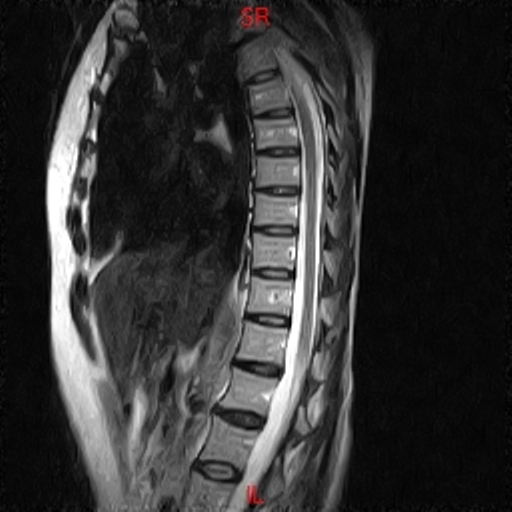

• RESONANCIA NORMAL COLUMNA DORSAL T2 SAGITAL